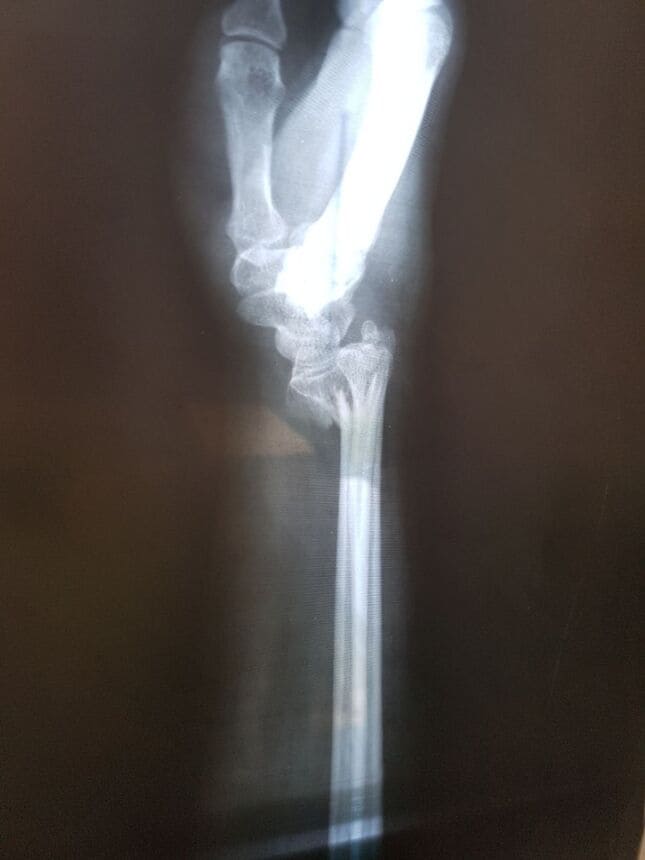

Fractura de radio distal